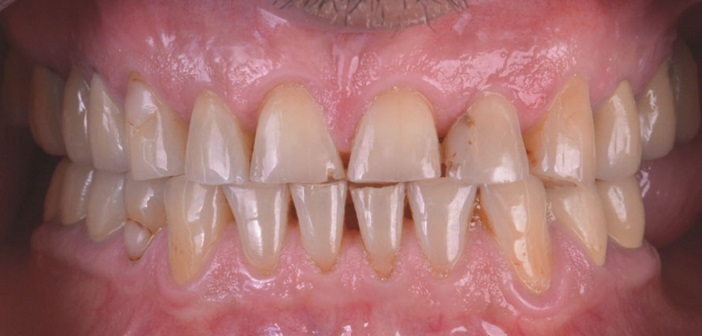

| Le patient âgé de 57 ans est demandeur d’une solution globale pour réhabiliter sa bouche. Pour élaborer le plan de traitement, nous suivons toujours le même chemin : discussion avec le patient pour connaître ses souhaits, désirs, limites en termes de traitement planification esthétique en utilisant l’outil Digital Smile Design (DSD) |

| Ces dernières années, l’évolution du collage a permis l’optimisation des traitements minimalement invasifs. Parfaitement adaptés aux attentes et aux besoins des patients présentant des usures, le collage permet la restauration d’une dent à la réhabilitation globale « full mouth ». |

| Il existe plusieurs formes d’usure dentaire (chimique, fonctionnelle, parafonctionnelle…) et chacune d’entre elles présente un tableau clinique spécifique. Nous associons souvent usure et bruxisme, pourtant ce dernier ne concerne qu’un faible pourcentage de patients atteints d’usure alors que l’usure dentaire est très fréquemment visible dans la bouche de nos patients. |